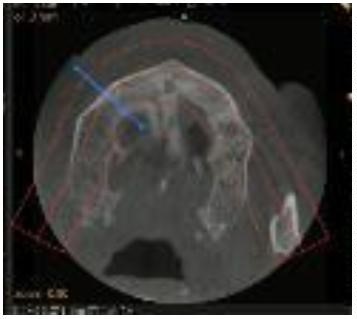

Para la planificación de la colocación de los implantes, la exploración clínica se complementa con la radiológica. La Radiografía Panorámica (OPG) (Figura 3) y la Tomografía Axial Computarizada (TAC) (Figura 4) nos permiten obtener la medición de los implantes y su punto de colocación.

Además, la Tomografía Computarizada de Haz Cónico (CBCT) nos informa sobre la cantidad y calidad ósea prequirúrgica. (Figura 5)